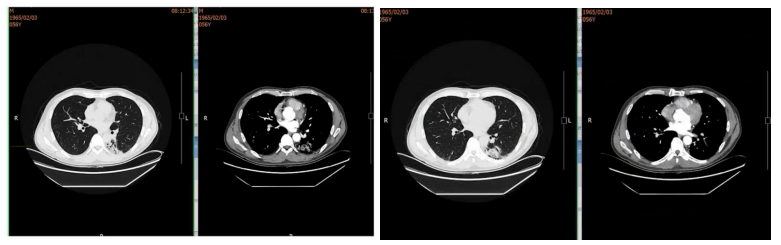

2021年10月起出现干咳伴发热(体温37.9℃),起初未重视,后咳嗽加剧伴咳白黏痰。11月15日于当地医院就诊,考虑肺炎,予青霉素联合阿奇霉素治疗一周,症状无改善。11月27日行胸部CT检查,提示左下肺斑片实变影,考虑继发性肺炎可能,给予泼尼松15mg BID一周、10mg BID一周治疗。治疗两周症状未缓解,且出现心悸气促,复查胸部CT病灶无吸收,遂自行停药,改服复方甘草合剂。两周后症状依旧,至第二家医院就诊,胸部CT显示肺部病灶增多变实,仍考虑继发性肺炎,予泼尼松30mg qd口服半月,气促稍有好转后又自行停药,期间辅以莫西沙星抗感染、乙酰半胱氨酸抗氧化治疗,复查胸部CT病灶仍无吸收,遂至我院。

胸部CTA:双侧胸廓对称,未见明显异常。双肺多发条索斑片影,左肺下叶为主。双侧肺门、纵隔、纵隔大血管和心脏影未见异常。纵隔内各组淋巴结未见异常肿大。双侧肋膈角和心膈角锐利。